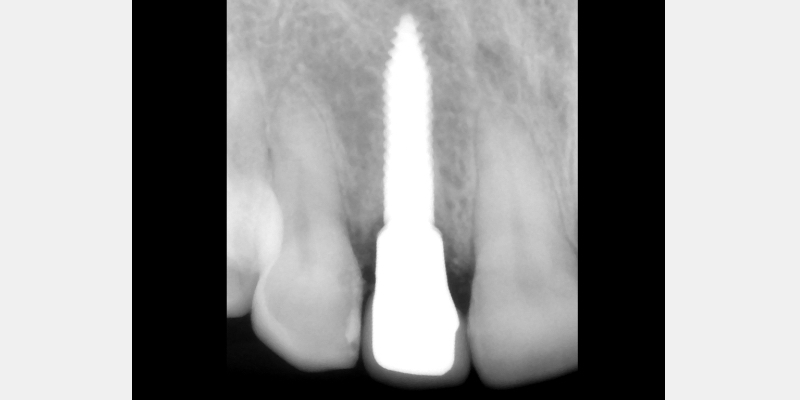

Silicone Jig Technique for Cement-Retained Implant Supported Restoration

One of the most common complications with cement-retained implant restorations is inflammation around the crown. Excess cement can lead to peri-implant diseases such as peri-implant mucositis and even bone loss. A key factor to understand is the biological difference between teeth and implants — particularly the structure of the junctional epithelium and connective tissue — which makes removing residual cement around the restoration more difficult.

Here is a simple, step-by-step technique for fabricating a silicone jig to avoid excess cement in a cement-retained implant-supported restoration. It can be applied to a single crown or to an implant-supported cement-retained bridge.